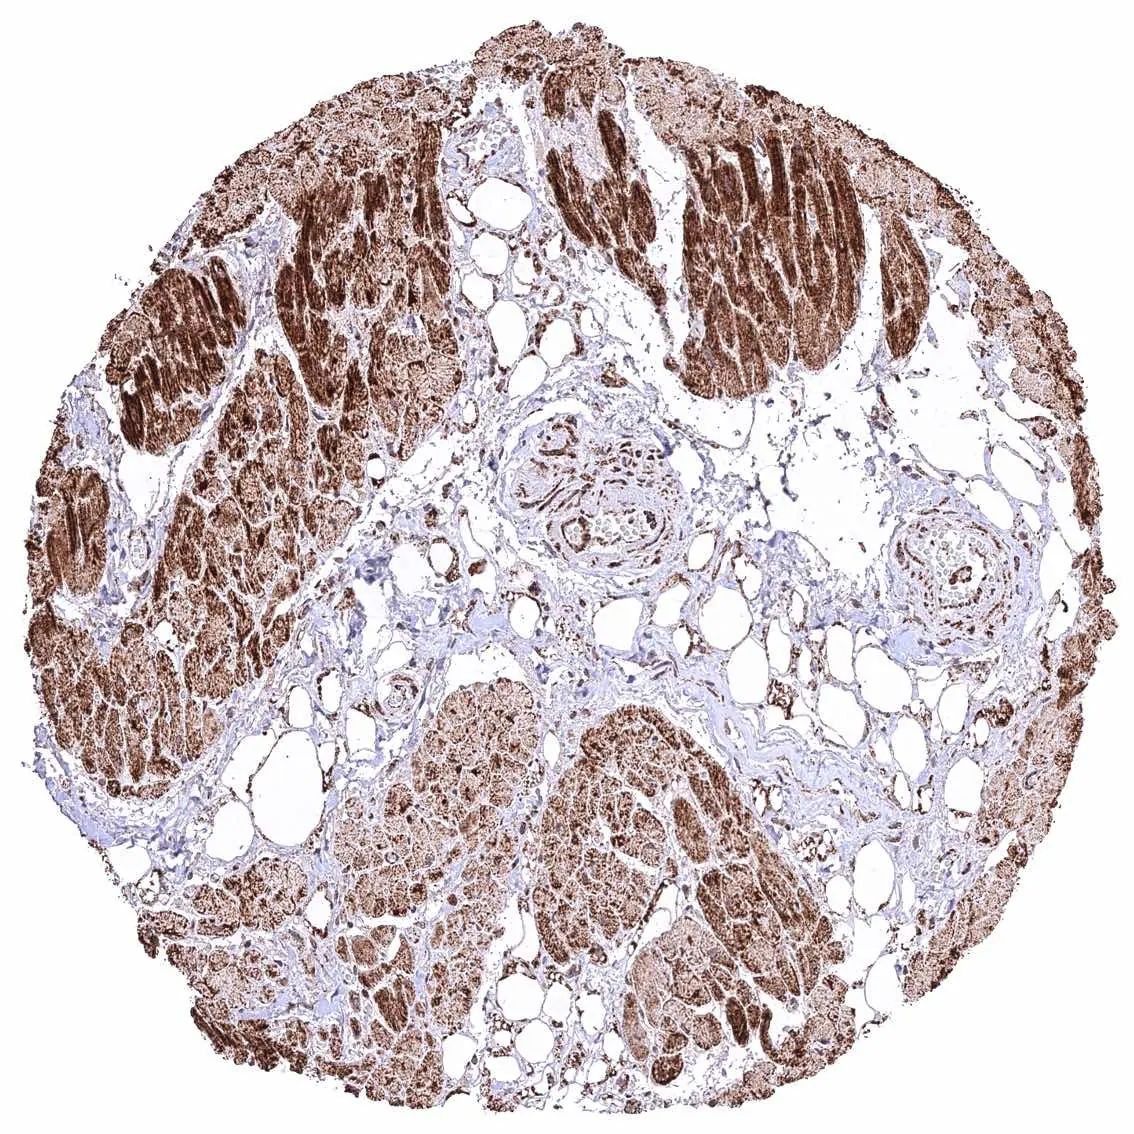

Skeletal muscle